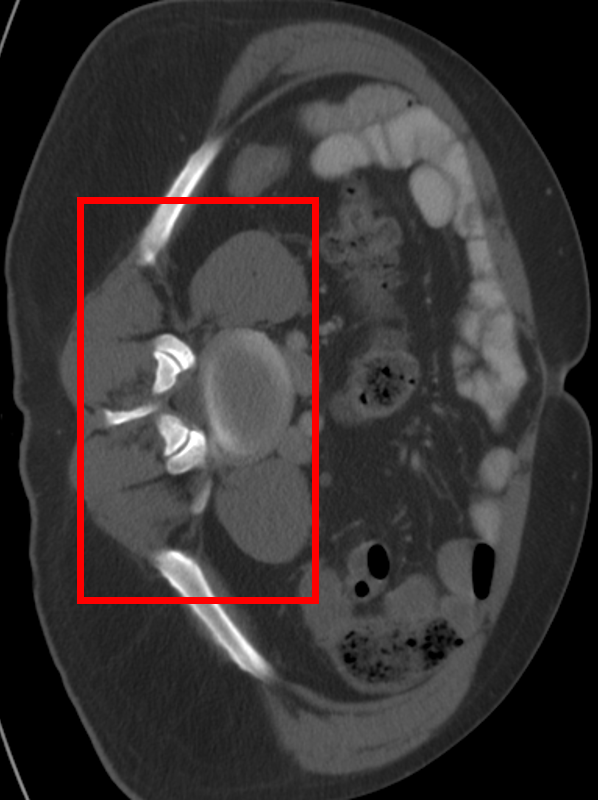

Refer to caption

\stackanchorGround Truth(a) x4

\stackanchorHRPSNR/SSIM

\stackanchorBicubic34.21/0.9700

\stackanchormDCSRN35.36/0.9770

\stackanchor3D MDSR35.42/0.9777

\stackanchor3D RDN36.17/0.9806

\stackanchorSAINT40.57/0.9888

\stackanchorGround Truth(b) x6

\stackanchorBicubic30.36/0.9400

\stackanchormDCSRN35.50/0.9711

\stackanchor3D MDSR36.26/0.9750

\stackanchor3D RDN35.46/0.9739

\stackanchorSAINT39.86/0.9863

Figure 7: Visual comparisons of different methods against SAINT. The difference maps are provided to the right of the results for better visualization. Images are best viewed when magnified.

In this section, we evaluate the performance of our method and other SISR approaches. Quantitative comparisons are presented in Table 2. MDCSRN uses a DenseNet structure with batch normalization, which has been shown to adversely affect performance in super-resolution tasks [17, 27]. Furthermore, inference with 3D patches lead to observable artifacts where the patches are stitched together, as shown in the mDCSRN results in Fig. 7.

For liver, colon and hepatic vessels datasets, SAINT drastically outperforms the competing methods; however, the increase in performance is less significant with the kidney dataset. Generalizing over unseen dataset is a challenging problem for all data-driven methods, as factors such as acquisition machines, acquisition parameters, etc. subtly change the data distribution. Furthermore, quantitative measurements such as PSNR and SSIM do not always measure image quality well.

We visually inspect the results and find that SAINT generates richer detail when compared to other methods. It is evident in Fig. 7 that there is a least amount of structural artifacts remaining in the different images produced by SAINT. For more discussion on SAINT’s advantage in resolving the memory bottleneck and more slice interpolation results, please refer to the supplemental material section.